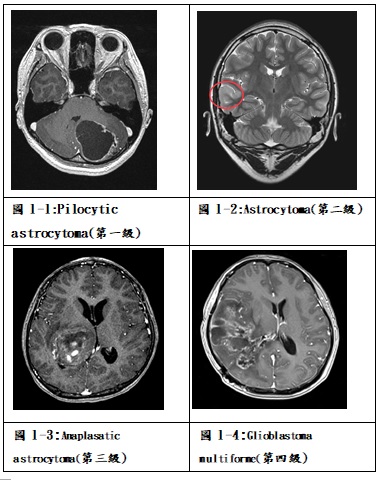

膠質細胞瘤約占兒童腦瘤的一半左右,其中包括幾種不同的病理診斷,如最常見的星狀細胞瘤(astrocytoma)、室管膜細胞瘤(ependymoma)、寡樹突神經膠質瘤(oligodendroglioma)、神經結神經膠質瘤(ganglioglioma)、及較少見的dysembryoplastic neuroepithelial tumor (DNET)、pleomorphic xanthoastrocytoma (PXA)及desmoplastic infantile ganglioglioma (DIG)。病灶的位置從大腦半球的表淺到深部丘腦、中腦、下視丘、視神經,或到位於後顱窩的小腦半球及橋腦及延髓均可能發生。影像學上常可見到在磁振造影上的不規則腫塊合併周邊腦組織的壓迫或偏移,可能在邊緣有顯影劑的加強,也可能不明顯,腫瘤中央可能形成水囊或局部壞死,腫瘤周圍可能有腦實質水腫的效應(圖1-1~4)。膠質細胞瘤中最常見的稱為星狀細胞瘤,病理上根據Daumas-Duport分類腫瘤細胞的型態為四級,第一級pilocytic astrocytoma和第二級astrocytoma稱為低度膠質瘤(low-grade gliomas),在文獻上這兩種類約各占星狀細胞瘤的三成,而第三級anaplastic astrocytoma和第四級glioblastoma multiforme稱為高度惡性膠質瘤(high-grade or malignant gliomas),僅占膠質瘤約兩成。由於膠質瘤依據不同位置及分類有不同的特性與治療方式,因此將特定部位的膠質瘤分別討論。